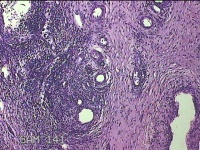

宫颈锥切物

性别

女

年龄

36岁

临床诊断

宫颈CIN2 宫颈乳头病毒感染

一般病史

检查发现CIN21个月。

标本名称

大体所见

灰白粉红色组织5.5x1.3x0.8cm一块,表面糜烂,切面灰白粉红色,质软,另有灰白粉红色组织2.3x2x0.3cm一堆,表面糜烂,切面灰白粉红色,质中。

图1